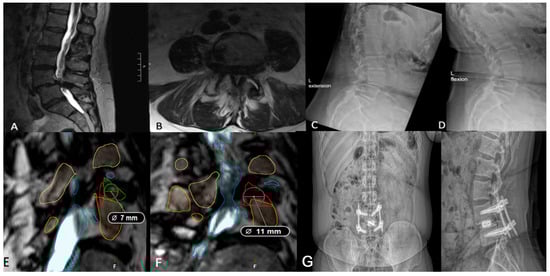

3.3. Measuring Kambin’s Triangle